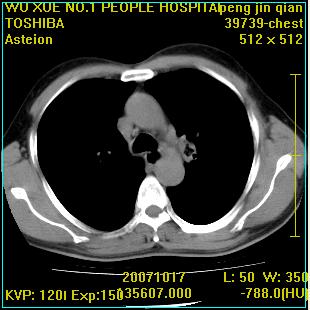

标题: CT10148:男,56岁,咳血。 [打印本页]

标题: CT10148:男,56岁,咳血。

左肺上叶尖段占位性病变,考虑肺癌.癌性空洞,并双肺转移灶及纵隔淋巴结转移

左肺上叶尖后段较大团块影,边缘光滑,内见不规则裂隙样空洞,周围明显见细小结节及渗出,与肺门方向结构紊乱,另:左上叶尖段外侧 舌叶内侧 右上叶尖段及下叶背段均见片状致密影。考虑:继发性肺结核伴空洞形成!

左上肺厚壁空洞影、两肺多发小片样不规则高密度灶。基本上能排除转移瘤。考虑肺结核伴空洞形成。

左上肺后壁空洞,内壁不规则,可见壁结节;左上叶尖段外侧 舌叶内侧 右上叶尖段及下叶背段均见片状致密影。考虑:左肺肺癌并两肺继发性肺结核?

左肺上叶尖后段较大团块影,边缘光滑,内见不规则裂隙样空洞,周围明显见细小结节及渗出,与肺门方向结构紊乱,另:左上叶尖段外侧 舌叶内侧 右上叶尖段及下叶背段均见片状致密影。考虑:继发性肺结核伴空洞形成!建议进一步检查,除外肺癌

右肺下叶背段/左上肺/左下肺结核伴空洞形成

结核 空洞伴两肺播散

浸润型肺结核伴左上肺空洞形成,两肺播散灶